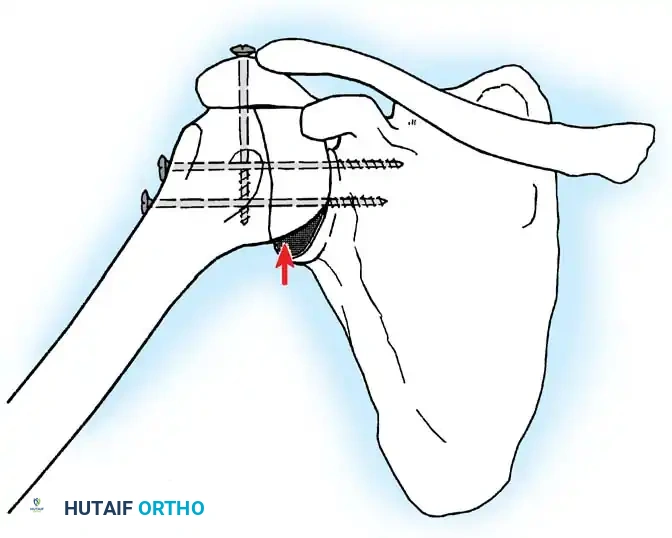

5. Rigid Internal Fixation

The most robust biomechanical construct involves a heavy, malleable plate (such as a 10- to 14-hole 4.5mm pelvic reconstruction plate or a dynamic compression plate). The plate is meticulously contoured to lie flat along the spine of the scapula, bend over the acromion, and extend down the lateral shaft of the humerus.

Screws are placed sequentially:

1. Scapular Spine: Cortical screws are placed into the dense bone of the scapular spine.

2. Acromiohumeral Fixation: Screws are passed through the plate, across the acromion, and into the humeral head.

3. Glenohumeral Fixation: Long, fully threaded cortical or cancellous screws are directed through the plate, through the humeral head, and deep into the glenoid neck and vault. This is the most critical step for achieving compression across the primary fusion site.

4. Humeral Shaft: The distal portion of the plate is secured to the humeral diaphysis.

If additional stability is required, or if bone quality is poor, a second plate (double plating technique) can be applied posteriorly.

Radiographic confirmation of a contoured reconstruction plate achieving rigid acromiohumeral and glenohumeral compression.